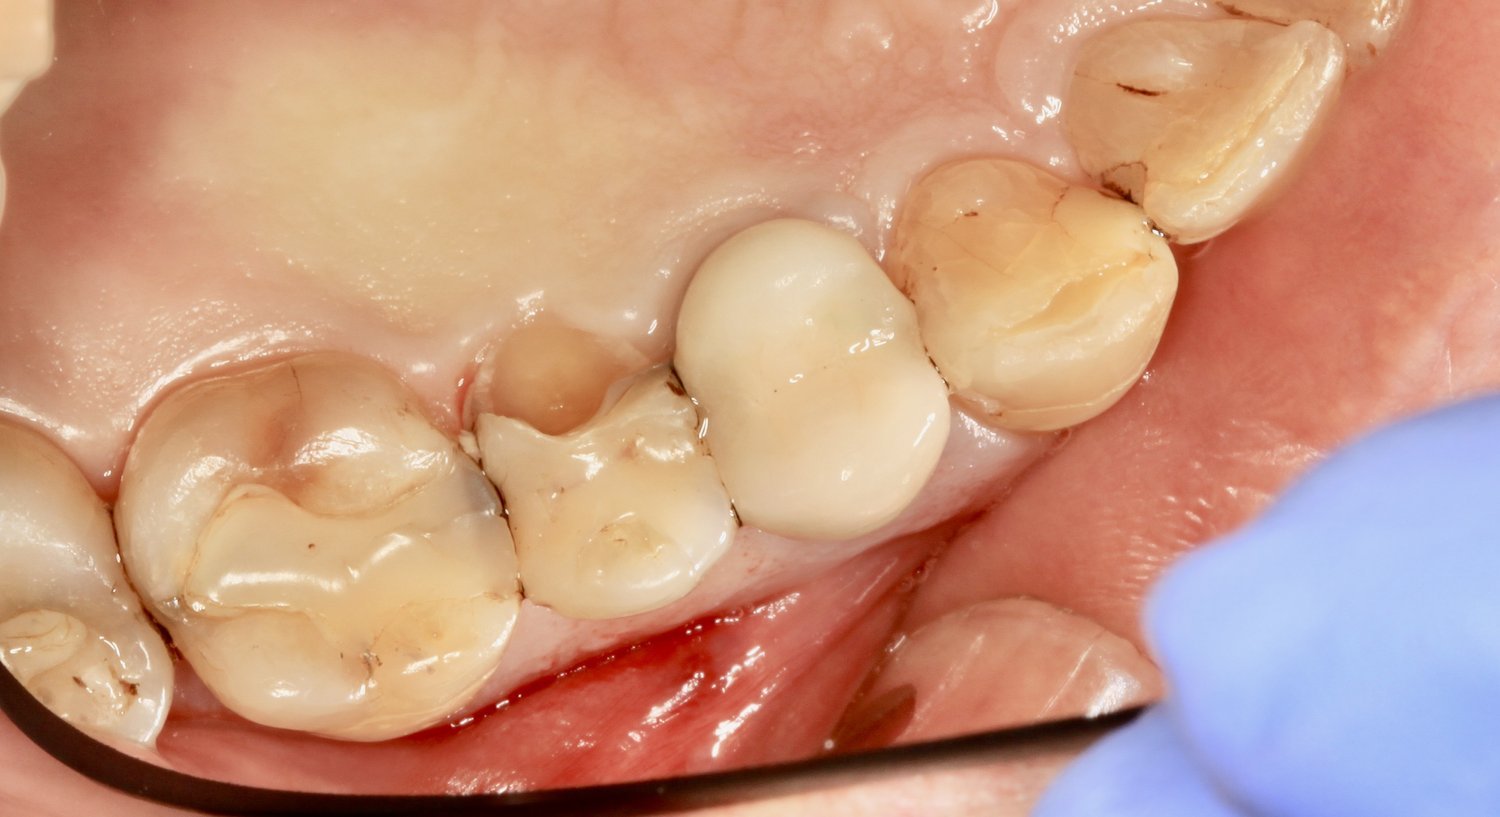

Before